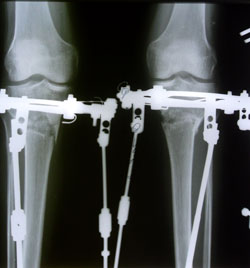

В процессе исправления деформации ног.